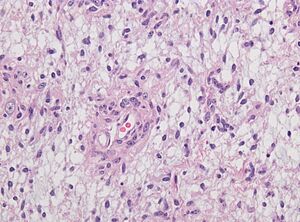

Neuropathology case V 03

A magnified view of brain tissue, showing signs of a condition called Angiocentric glioma.